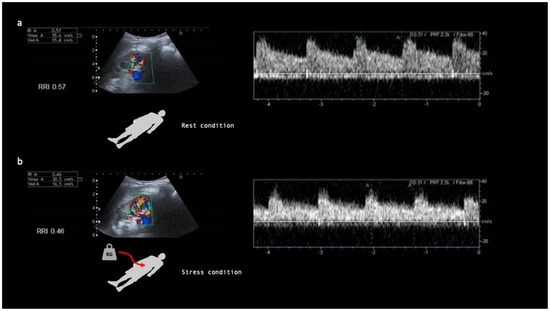

- Samoni, S.; Nalesso, F.; Meola, M.; Villa, G.; De Cal, M.; De Rosa, S.; Petrucci, I.; Brendolan, A.; Rosner, M.H.; Ronco, C. Intra-Parenchymal Renal Resistive Index Variation (IRRIV) Describes Renal Functional Reserve (RFR): Pilot Study in Healthy Volunteers. Front. Physiol. 2016, 7, 286. [Google Scholar] [CrossRef]

- Samoni, S.; Villa, G.; De Rosa, S.; Husain-Syed, F.; Guglielmetti, G.; Tofani, L.; De Cal, M.; Nalesso, F.; Meola, M.; Ronco, C. Ultrasonographic Intraparenchymal Renal Resistive Index Variation for Assessing Renal Functional Reserve in Patients Scheduled for Cardiac Surgery: A Pilot Study. Blood Purif. 2022, 51, 147–154. [Google Scholar] [CrossRef]